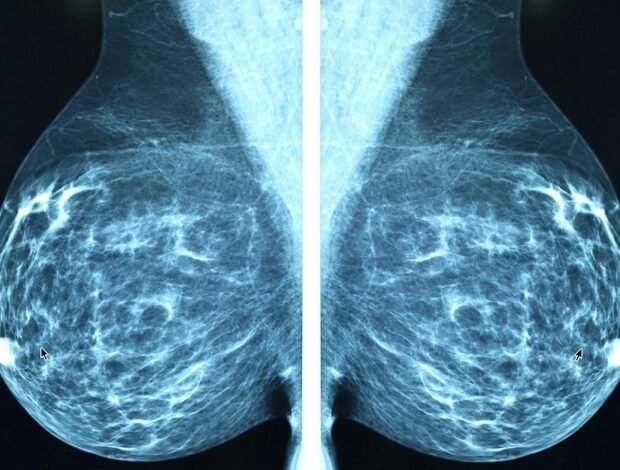

O estudo traz esperança para uma abordagem mais personalizada para o tratamento do câncer de mama ER+

Um novo estudo de pesquisadores da Baylor College of Medicine traz esperança em uma abordagem mais personalizada para o tratamento de receptores positivos do câncer de mama (ER+), que é o tipo mais comum nesse câncer. A equipe identificou uma marca vibrante no ER+ antes dos modelos clínicos de câncer de mama que indicam que o tumor provavelmente responderá aos inibidores CDK4/6. Os resultados apóiam mais estudos clínicos para determinar se essa marca pode ajudar a identificar pacientes que podem se beneficiar dos inibidores de CDK4/6. O estudo apareceu em Medicina científica.

O câncer de mama ER+ depende do estrogênio para crescer e geralmente tratar através de tratamentos endócrinos que impedem os efeitos do estrogênio. Para melhorar os resultados, os medicamentos chamados inibidores de CDK4/6, como abemaciclib e ribociclib, são adicionados ao tratamento endócrino para evitar recaídas. Como resultado, muitos pacientes são expostos a terapia prolongada com inibidores de CDK4/6 (até três anos) e efeitos prejudiciais sem uma compreensão verdadeiramente clara desses fatores.